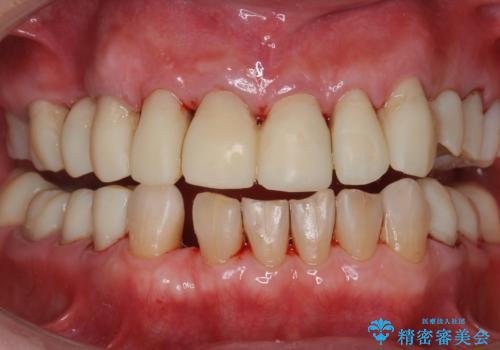

ステインがたくさん付着していたので、エアフローを用いてステインを除去しました。そのため、直後の写真は歯肉からの出血が見られます。